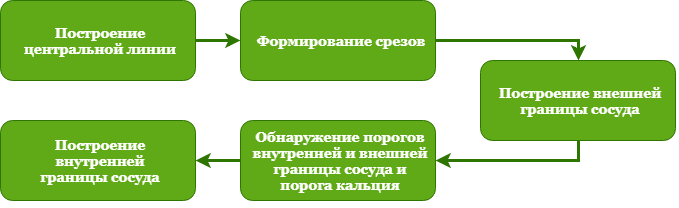

Чтобы оценить сужение сосуда, нам нужно знать просвет сосуда или его внутреннюю границу. Для этого нужно как минимум обнаружить весь кальций. Также мы находим внешнюю границу, потому что она дает возможность оценить толщину стенки, что также полезно. Для начала давайте взглянем на полную схему обнаружения границ, а затем подробно разберем каждый этап:

Построение центральной линии

Формирование срезов

Построение внешней границы сосуда

Обнаружение порогов внутренней, внешней границ и порога кальция

Построение внутренней границы сосуда